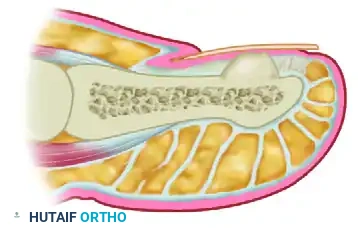

The subungual space is a unique anatomic and biomechanical environment. The perionychium—comprising the nail plate, nail bed (sterile and germinal matrices), and surrounding soft tissue folds—serves critical functions in tactile sensation, thermoregulation, and protection of the distal phalanx. Pathologic entities arising in this confined space, such as subungual fibromas, subungual exostoses, and glomus tumors, often present with disproportionate pain and nail dystrophy due to the rigid boundaries of the nail plate dorsally and the distal phalanx volarly.

The glomus tumor is an enigmatic, exquisitely painful neoplasm that represents a benign hamartomatous proliferation of the normal capsular-neural glomus apparatus (the Sucquet-Hoyer canal). These neuromyoarterial bodies are highly concentrated in the subungual reticular dermis and are responsible for thermoregulation via arteriovenous shunting.

Except for a faint bluish or reddish-blue hue visible through the translucent nail plate, the nail itself may appear entirely normal. The pathology lies entirely within the mass seen through the nail plate.